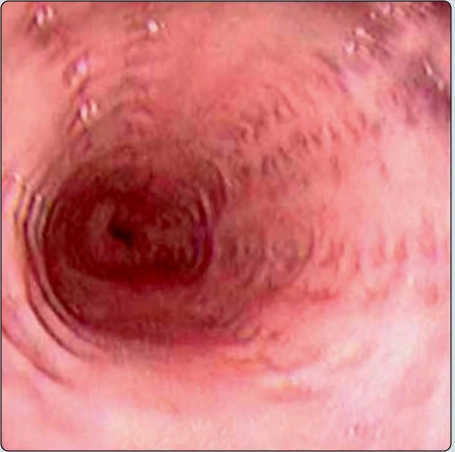

Túi thừa zenker (Zenker diverticulum)

• Túi thừa zenker (Zenker diverticulum)